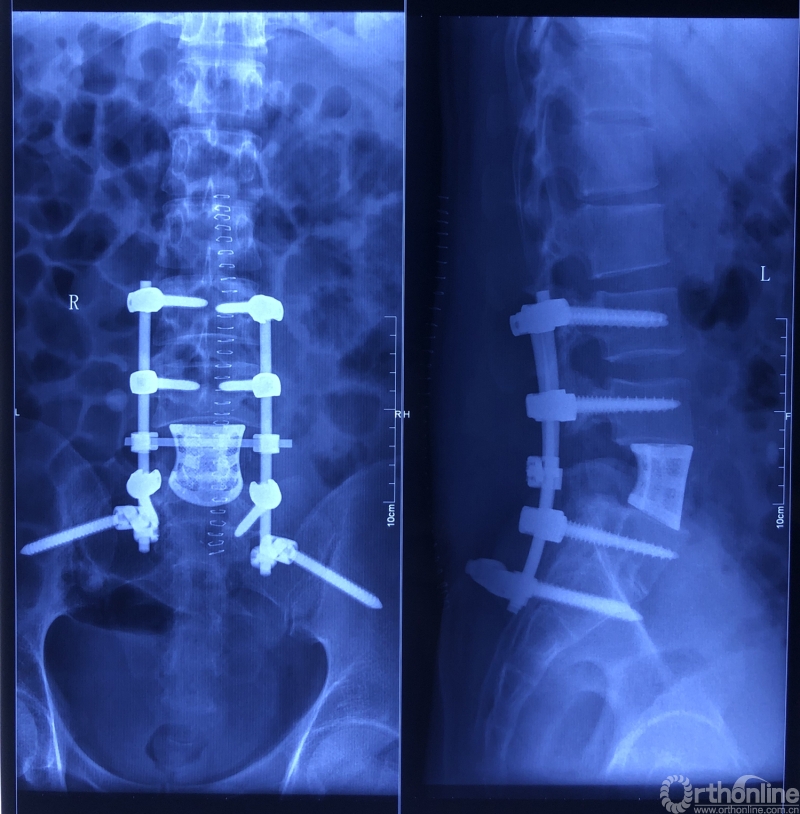

在三大技术的保驾护航以及李锋教授高超的手术技巧下,手术顺利结束。肿瘤和被侵蚀的椎体被切除,人工椎体被两根矫形棒和八颗螺钉稳稳固定在脊椎缺口处,脊柱结构重建。与传统手术方案相比,患者创伤减少,软组织及血管、神经等破坏更少,肿瘤清除更彻底,局部肿瘤复发率更低。术后患者生命体征平稳,安返病房。病灶已送检,将根据病检结果指导进一步的治疗。目前,病人神志清醒、腰痛缓解、恢复良好。

术后X线片

固定人工椎体时,李锋教授一边使用计算机辅助导航设备在田先生脊柱上探测、一边抬头看手术床尾的计算机屏幕,依据屏幕显示来导航,精准定位、寻找合适的植钉位置。

计算机导航精准定位椎弓根螺钉进钉位置、角度、深度